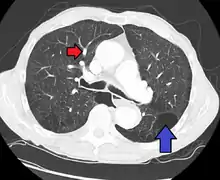

CT scan

Signs of pulmonary hypertension on CT scan of the chest are:

- Enlargement of the pulmonary trunk (measured at its bifurcation). It is, however, a poor predictor of pulmonary hypertension in patients with interstitial lung disease.[61]

- A diameter of more than 27 mm for women and 29 mm for men is suggested as a cutoff.[61]

- A cutoff of 31.6 mm may be a more statistically robust in individuals without interstitial lung disease.[61]

- Increased ratio of the diameter of the main pulmonary artery (pulmonary trunk) to the ascending aorta (measured at its bifurcation).

- Increased diameter ratio of segmental arteries to bronchi. This finding in three or four lobes, in the presence of a dilated pulmonary trunk (≥29 mm), and absence of significant structural lung disease confers a specificity of 100% for pulmonary hypertension.[61]

- Mural calcification in central pulmonary arteries is most frequently seen in patients with Eisenmenger's syndrome.[61]